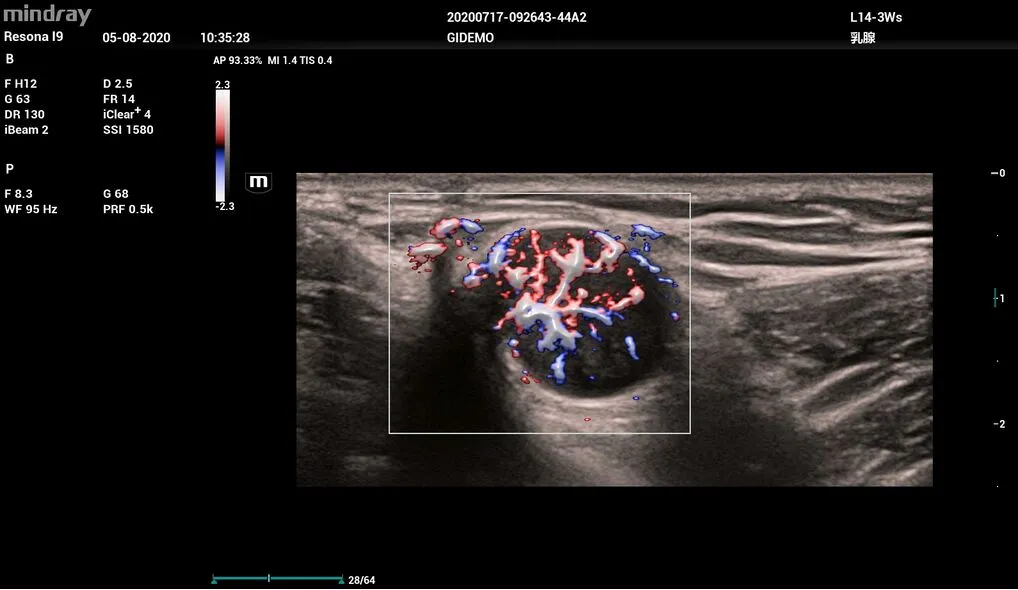

- HR Flow™ (отображение кровотока с высоким пространственным и временным разрешением)

- Smart Breast (интеллектуальный анализ заболеваний молочной железы по шкале BI-RADS)

Диагностика заболеваний молочной железы Smart Breast

Resona I9 позволяет проводить интеллектуальный анализ молочной железы по шкале BI-RADS, включая полностью автоматическое обнаружение, измерение, аннотирование, анализ поражений, составление отчётов. Протокол ориентирован на очаги поражения, что повышает контроль качества. Множественные поражения могут исследоваться в нескольких плоскостях для получения более полных данных.

- L14-3Ws – линейный датчик для исследования сосудов, органов брюшной и грудной полости, педиатрии.

Рак груди, 2D, L14-3Ws

Опухоль, L14-3Ws